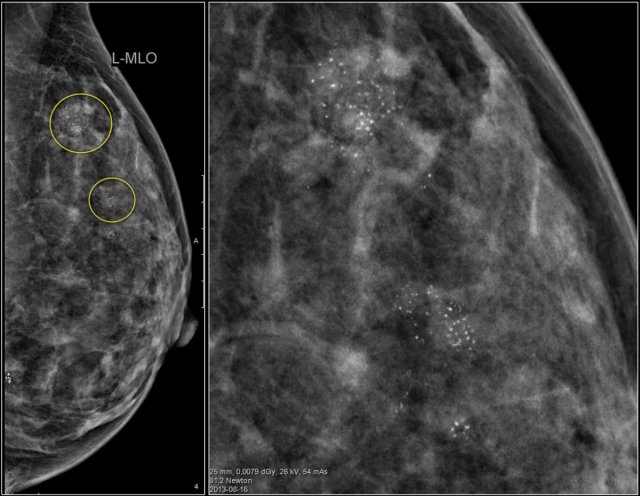

Study the images and describe the calcifications.

Then continue reading.

The findings are:

• Morphology: some are coarse heterogenous and some look more like fine pleomorphic.

• Distribution: Some calcifications are in a group ( <2cm) and some are in a regional distribution ( >2cm), but not in a segmental or linear arrangement.

This proved to be multifocal DCIS with areas of invasive carcinoma.